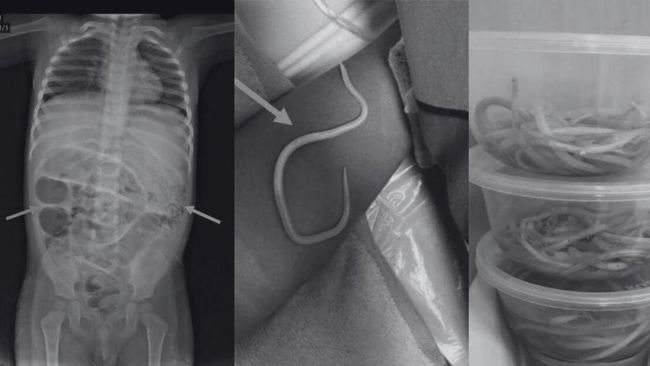

Ilustrasi cacing bersarang (Foto: Journal of Medical Case Reports)

• Cacing Gelang (Ascaris lumbricoides): Dikutip dari jurnal Universitas Brawijaya, pada infeksi ringan, mungkin tidak ada gejala. Namun, jika jumlah cacing di usus sangat banyak, dapat menyebabkan penyumbatan usus. Dalam kasus yang jarang terjadi, cacing dewasa dapat keluar dari tubuh melalui mulut, hidung, atau anus, yang menjadi tanda diagnosis yang pasti (repository.ub.ac.id).

3. Pemeriksaan Lainnya: Dalam kasus tertentu seperti dugaan neurosistiserkosis, tes pencitraan seperti CT scan atau MRI mungkin diperlukan. Selain itu, diagnosis dapat dikonfirmasi jika cacing dewasa terlihat keluar dari tubuh.